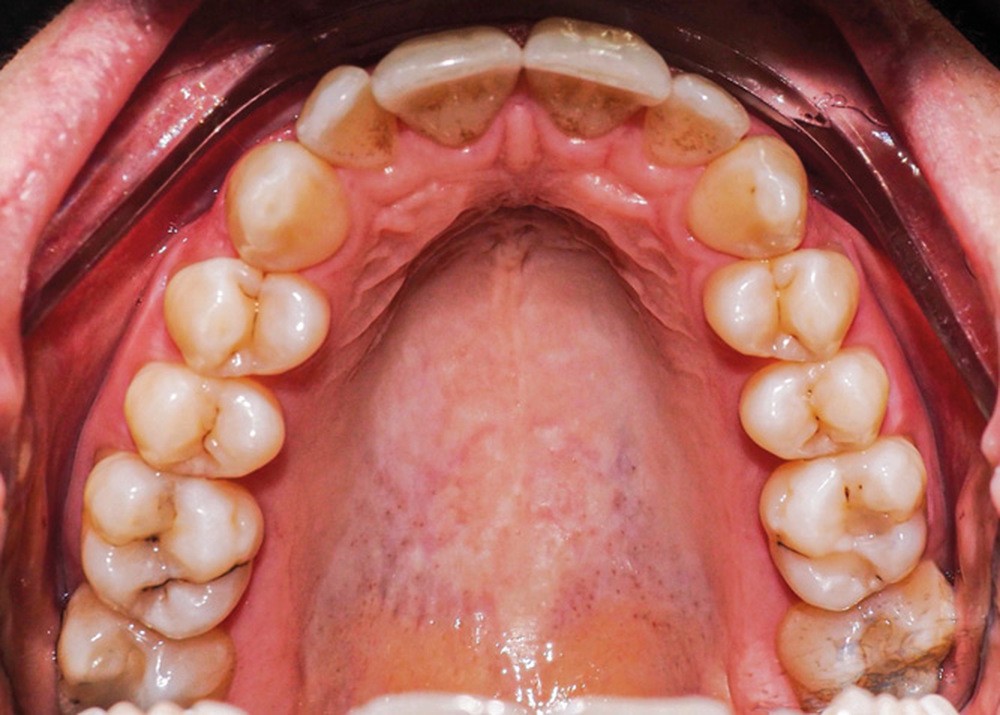

Examen endo-buccal (fig. 2a-e)

L’arcade maxillaire est parabolique, la 12 présente une légère mésio-rotation. L’arcade mandibulaire est également parabolique avec un encombrement antérieur estimé à 6 mm. On note une dyschromie de la 31, dont le test de vitalité est négatif. Le parodonte est fin.

Les incisives maxillaires sont de forme triangulaire [1] et l’indice de Bolton est de 97 % qui traduit la présence d’une DDD par excès mandibulaire.